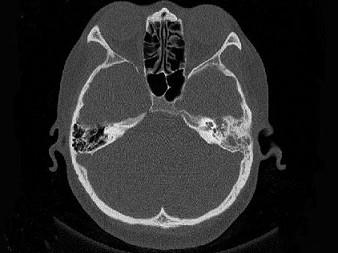

女,34岁,左耳鸣,听力下降两个月,PE:左外耳道有脓性分泌物,鼓膜充血水肿,左中耳腔内软组织影,CT检查如图,最可能诊断为 ( )